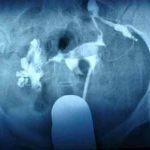

大多数输卵管积水患者症状不明显,超声和输卵管碘油造影是诊断输卵管积水的主要手段。腹腔镜也可明确诊断输卵管积水,但是由于是一个有创手术,且费用较高,一般不作为常规的检查方式。